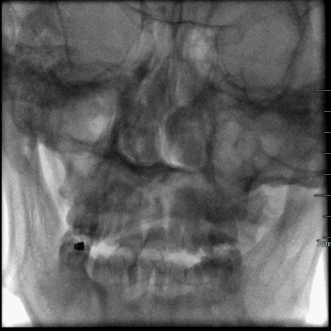

术后即刻CT

术后24小时CT

术后DWI